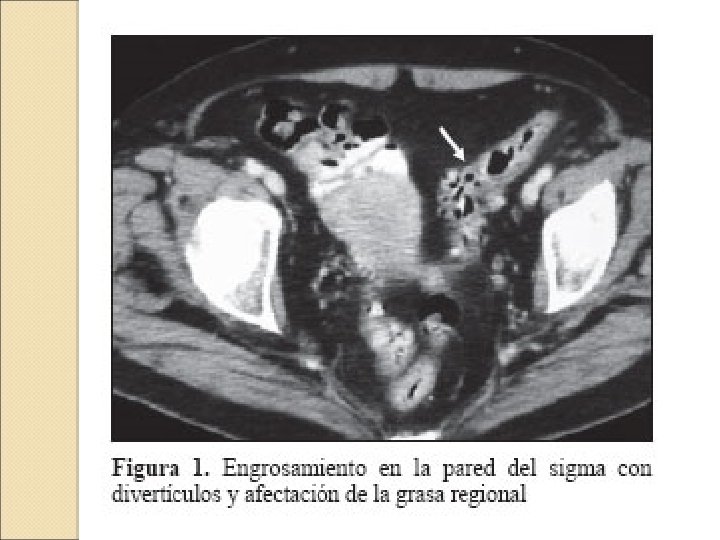

Agosto: �Se realiza un nuevo ciclo de Ciprofloxacino + Metronidazol �TAC abd: abd Cambios inflamatorios en la grasa adyacente con pequeñas adenopatías y varios divertículos sugerentes de diverticulitis. No líquido libre ni colecciones. �Ante la no mejoría del cuadro se propone ingreso hospitalario, pero la paciente lo rechaza y pasa a cargo de H. Domicilio